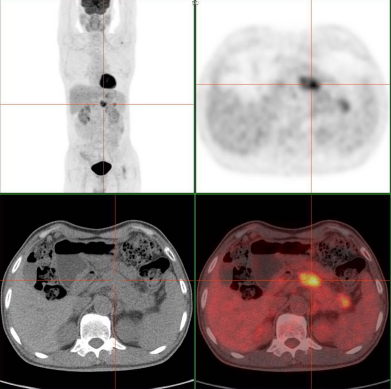

做一次 PET/CT,全身肿瘤都能查出来?这是很多人对这项高端影像检查的疑问。PET/CT 确实是目前肿瘤诊断领域的“利器”,它结合了 PET(正电子发射断层显像)的功能代谢探测和 CT 的解剖结构显示,能像“雷达”一样捕捉全身异常活跃的肿瘤细胞。但并非所有人都需要做,以下 5 类人群才是真正的“刚需”。

对于刚确诊癌症的患者,PET/CT可以明确肿瘤分期。比如肺癌患者,通过一次扫描就能清楚判断肿瘤是否转移到纵隔淋巴结、肝脏、骨骼等部位,医生据此制定手术、化疗还是靶向治疗的方案。有数据显示,约 20% 的癌症患者通过 PET/CT 检查后,会改变原有的治疗计划。

治疗中的患者也需要定期做 PET/CT 评估疗效。化疗或放疗后,肿瘤是否缩小、活性是否降低,传统检查可能难以准确判断,而 PET/CT 能通过肿瘤细胞对显像剂(如 18F-FDG)的摄取量变化,直观反映治疗效果。如果肿瘤仍有高代谢活性,提示可能需要调整治疗方案。

癌症具有转移特性,有些患者会出现不明原因的骨痛、头痛或体重骤降,怀疑肿瘤转移却找不到具体位置。这时 PET/CT 就能发挥优势,它能一次性扫描全身骨骼、脑部、内脏等部位,精准定位转移灶。例如乳腺癌患者出现腰背痛,PET/CT 可明确是否发生骨转移,比骨扫描更敏感,还能同时排查其他部位的转移情况。